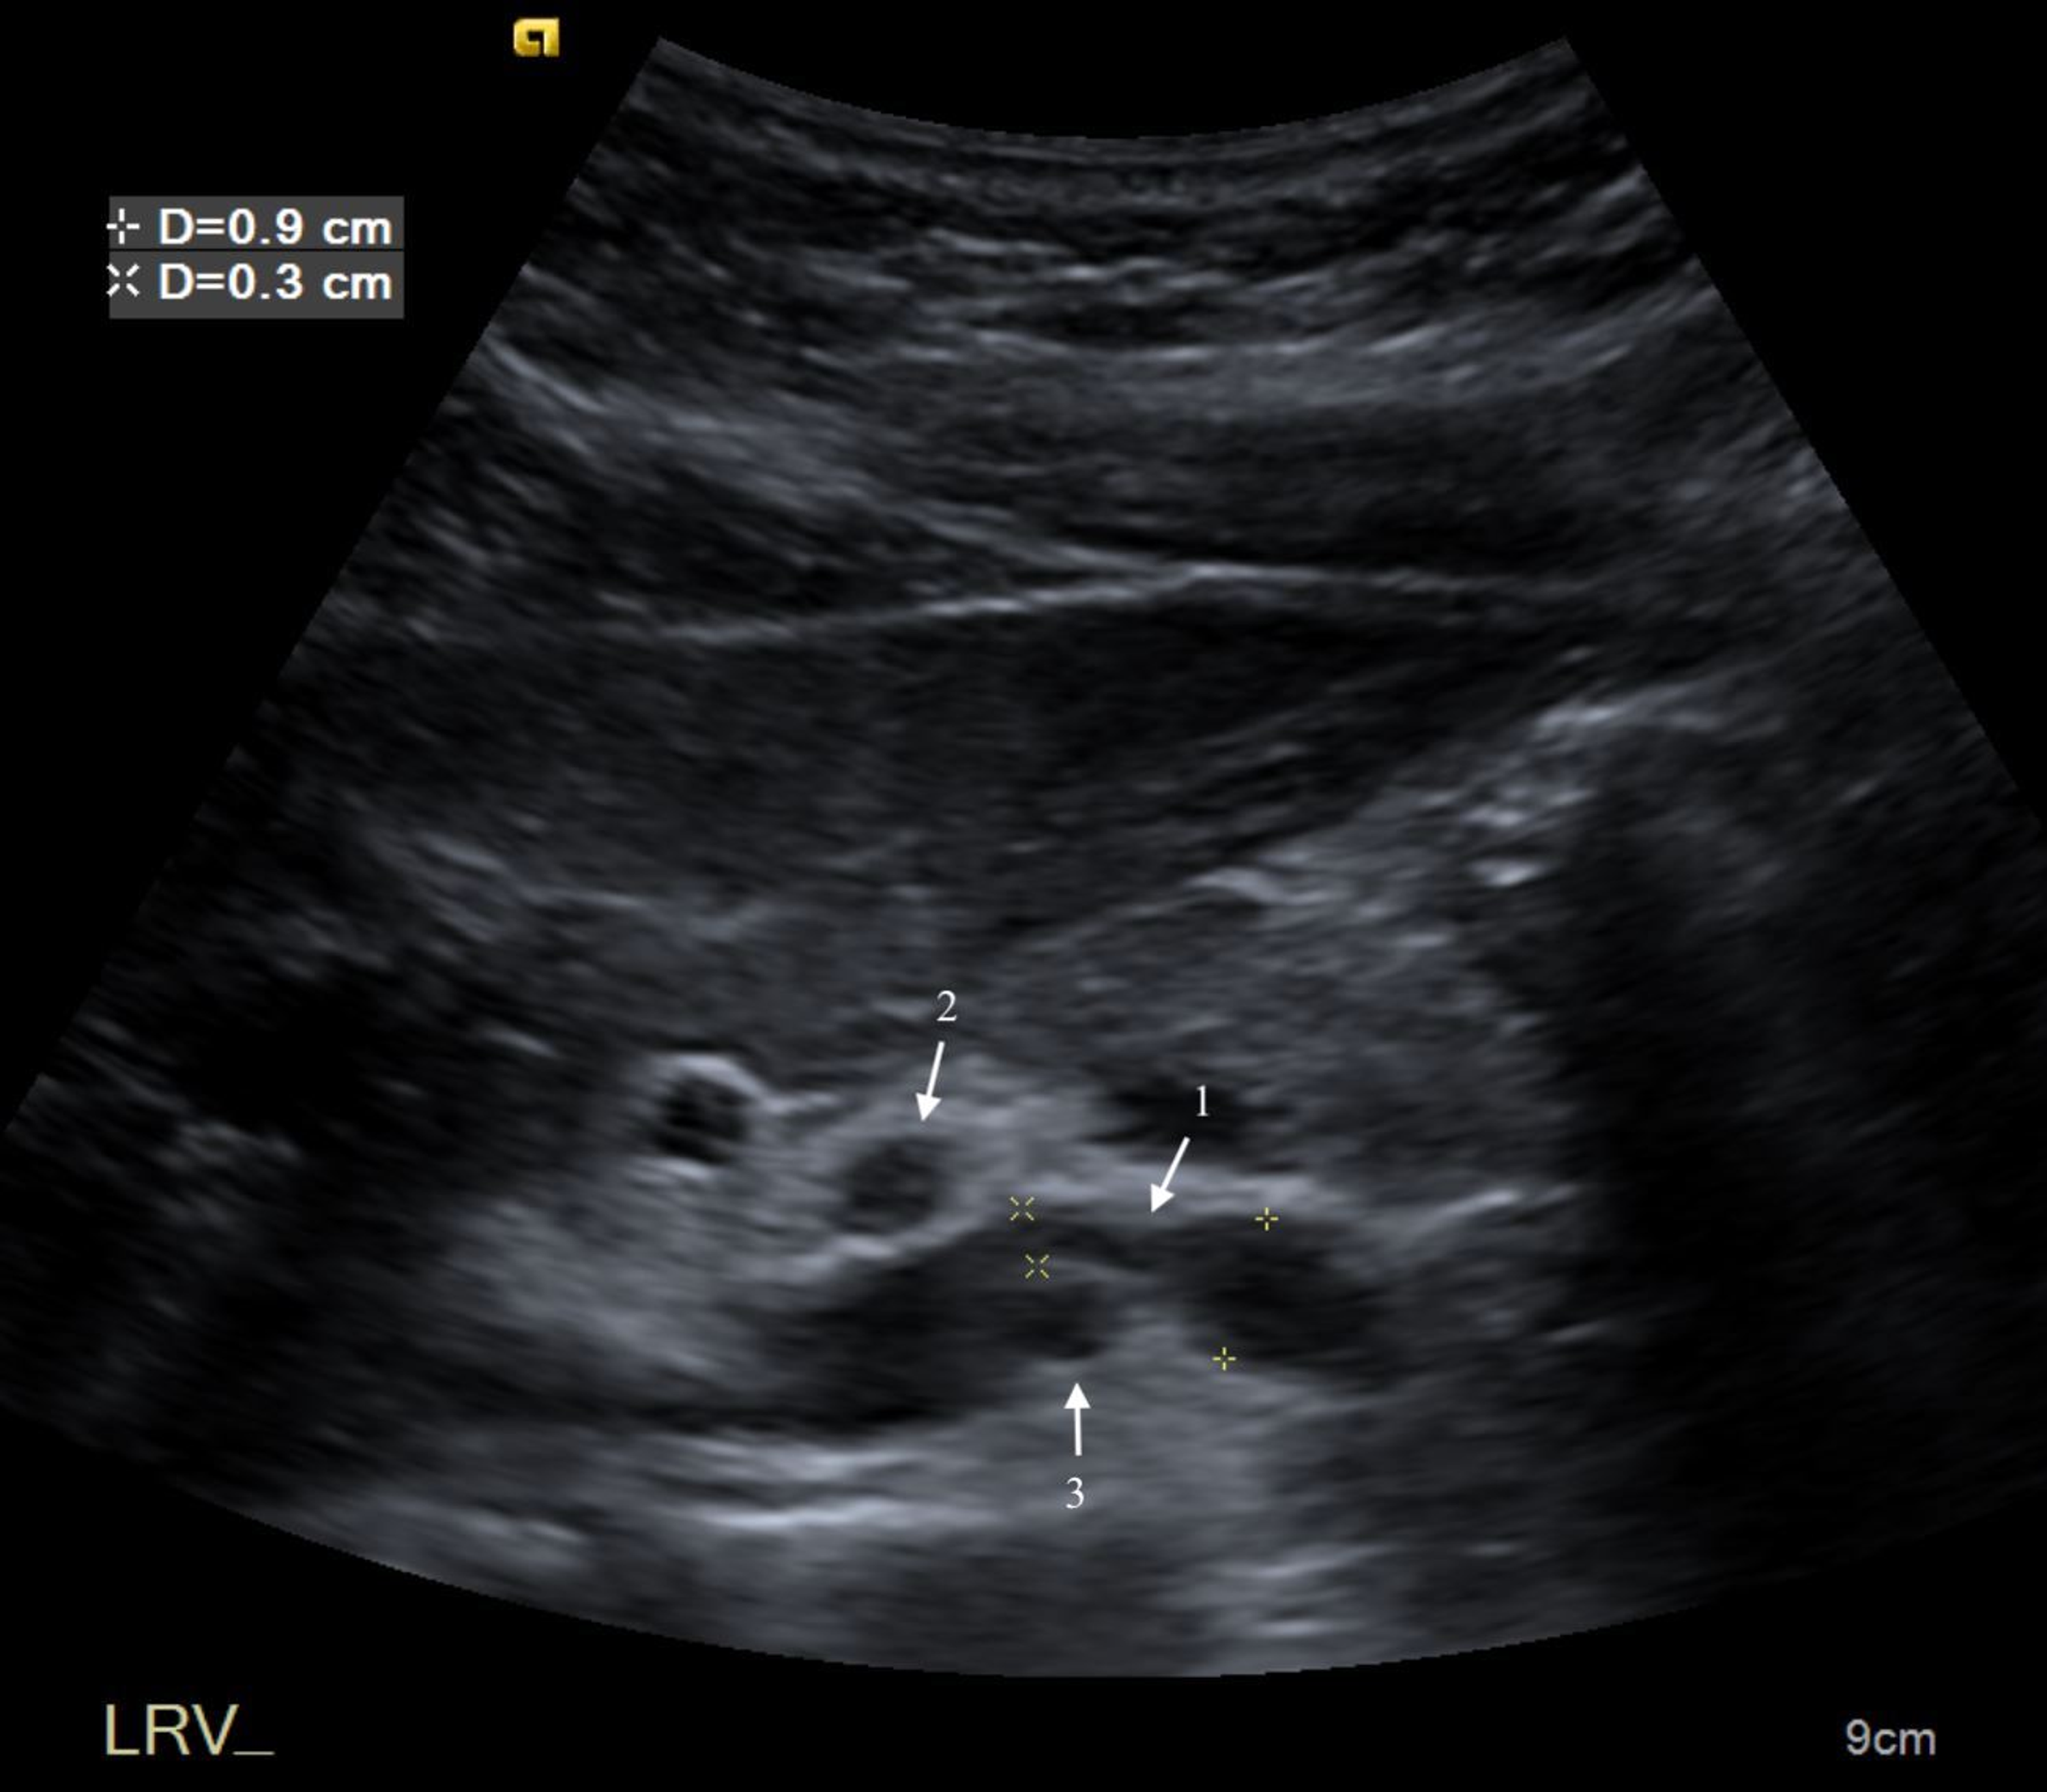

From sonographictendencies.com

Nutcracker Phenomenon/Syndrome Sonographic Tendencies Nutcracker Syndrome Pain Patients most commonly present with unexplained hematuria and flank or pelvic pain, which can be severe at times. Often, patients have had several emergency room visits for pain. Nutcracker syndrome (ns) is a condition in which the left renal vein becomes compressed. These symptoms are due to the left. Nutcracker syndrome is a rare vein compression disorder. This can restrict. Nutcracker Syndrome Pain.